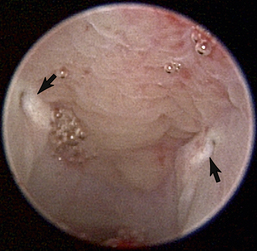

The hallmark symptom of nasopharyngeal disease is stertor. Discharge, sneezing, reverse sneezing, and hacking may be present variably. If the main complaint is noisy breathing and not productive sneezing with nasal discharge, the nasopharynx may be the site of primary disease. The most common primary problems in the nasopharynx in cats are inflammatory polyps and tumors.12,13 Cats with polyps are generally young and have a history of noisy breathing. Sneezing and mucopurulent nasal discharge may be present, but the chief complaint is stertor and increased respiratory effort. This is a problem that often requires otoscopic as well as rhinoscopic intervention. With the patient placed in dorsal recumbency, the soft palate is reflected rostrally with the use of a spay hook, and the polyp is removed via traction and avulsion (Figures 19-18 and 19-19). The eustachian tube orifices can generally be directly visualized and any remaining tissue removed, if present. Both ears should be carefully examined, and transtympanic bulla curettage should be performed to remove any middle ear proliferative tissue (see Chapter 20). In older cats with similar symptoms, a neoplasm in the nasopharynx is more likely, and rhinoscopy is often much more rewarding (Figure 19-20). Foreign bodies can become lodged in this area after vomiting or pharyngeal nasopharyngeal spasms induced by attempted swallowing of the foreign object. Nasal and nasopharyngeal stenosis after trauma, nasogastric reflux,14 and chronic rhinitis can occur in dogs and cats (Figures 19-21 through 19-23). Reflux can occur during general anesthesia and can be a helpful clue if postoperative symptoms arise and persist. Congenital choanal atresia and nasopharyngeal dysgenesis have also been reported in dogs.15,16 Nonspecific chronic inflammation of the nasopharynx causes a cobblestone appearance of the mucosa due to the formation of hyperplastic lymphoid follicles (Figures 19-24 and 19-25). Chronic inflammation may be the result of a lymphoplasmacytic rhinitis complex or sometimes may be secondary to otitis media and middle ear drainage of infected secretions via the eustachian tube. Otoscopy is recommended in any patient with nasopharyngitis of unknown origin. CT studies performed in a population of 45 cats with chronic sinonasal discharge revealed effusive bulla disease in 28% of symptomatic cats.17 Unfortunately, we are unable to differentiate primary and secondary pathology based on the concurrence of nasal and middle ear disease. Regardless of the knowledge of the primary cause, both inflammatory foci should be treated to achieve symptom relief.

image

Figure 19-19 Feline benign nasopharyngeal polyp extraction.